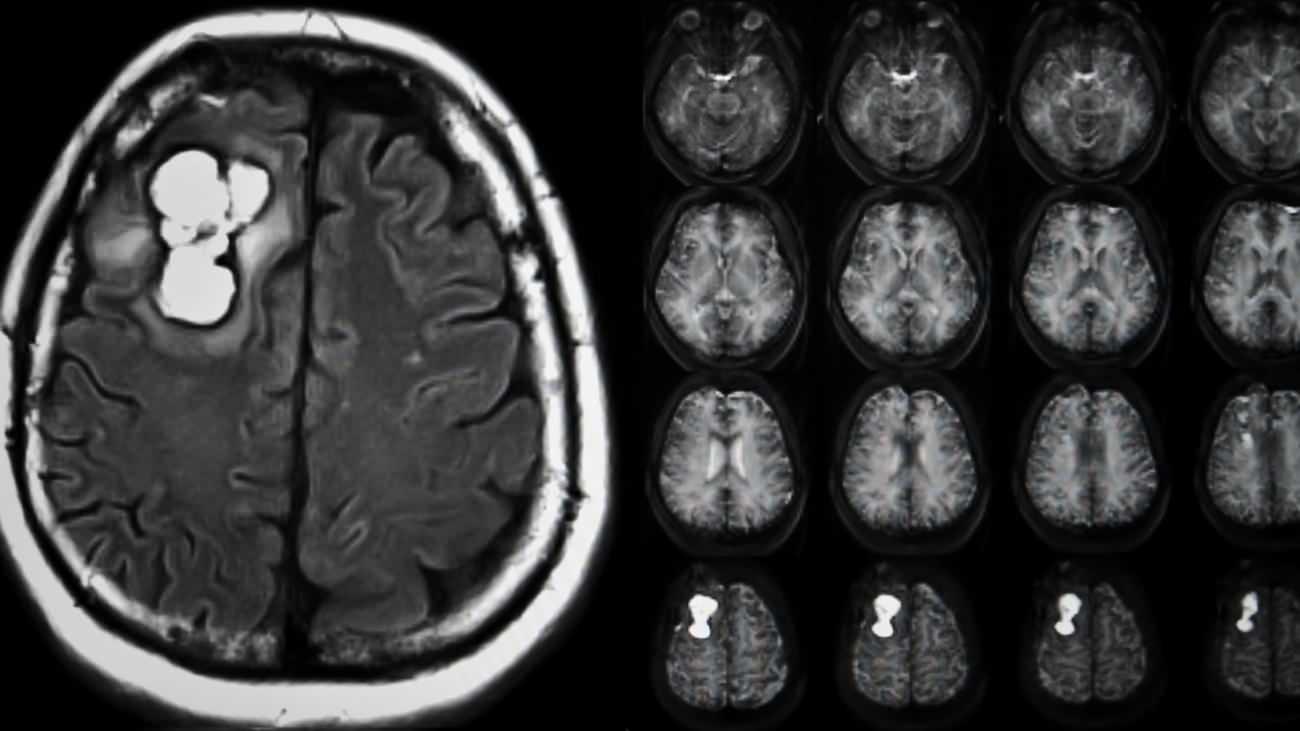

Beyin tümörlerinin kesin tanısı için MR çekiminin altını çizen Dr. Gökçek, “Kapalı alan korkusu olan hastalar için tomografi kısa sürede bilgi verebilir. Ancak beyin tümörlerinin doğru şekilde tespiti ve lokalizasyonu için MR şarttır” diye konuştu.